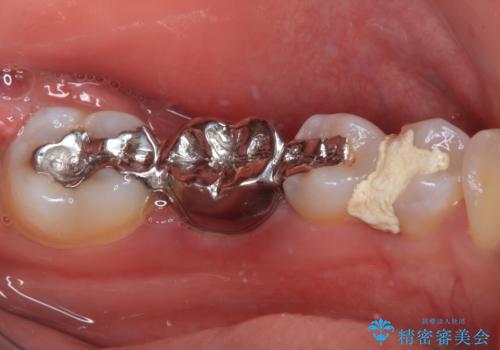

- ブリッジの歯のないところにインプラントを入れて、銀歯を白くやり替えたいと来院された患者様です。

歯の欠損している箇所にはインプラント治療をし、銀歯と仮詰めの部分はセラミックインレーにて補綴することとしました。

すべての治療の前に親知らずの抜歯も行っています。